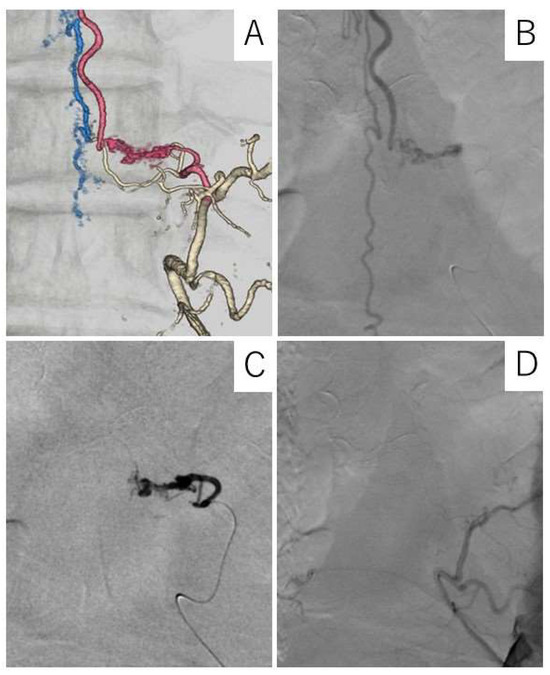

Case Description